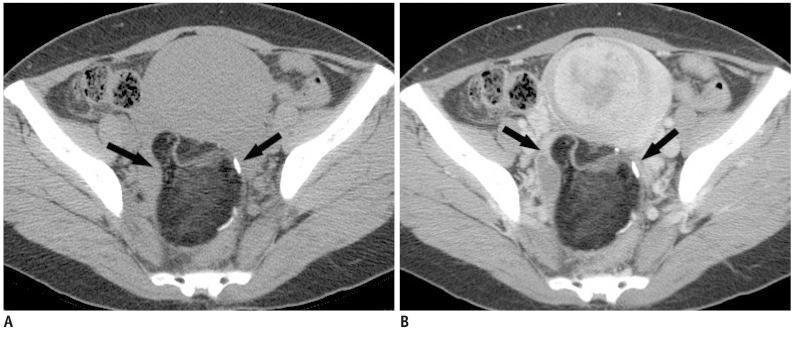

多排螺旋 CT 在附件包块评估中的应用:平扫 CT 是否有必要?

Multidetector computed tomography for the assessment of adnexal mass: is unenhanced CT scan necessary?

To compare the diagnostic performance and radiation dose between contrast-enhanced CT (ECT) alone, and combined unenhanced and contrast-enhanced CT (UE + ECT) for the assessment of adnexal mass.

Of the total 178 adnexal masses, 133 masses were benign and 45 masses were malignant. For both readers, there is no significant difference of AUC values between ECT alone and UE + ECT for the detection of adnexal malignancy (reader 1, 0.93 vs. 0.95; reader 2, 0.92 vs. 0.91) (p > 0.05). The mean CTDIvol (12.6 ± 2.2 mGy) and DLP (641.2 ± 137.2 mGy) of ECT alone was significantly lower than the mean CTDIvol (21.5 ± 2.7 mGy) and DLP (923.6 ± 158.8 mGy) of UE + ECT (p < 0.0001).

The use of unenhanced CT scan in addition to contrast-enhanced CT scan does not improve the detection of adnexal malignancy, but increases radiation exposure.

比较单独对比增强 CT(ECT)与联合平扫和增强 CT(UE + ECT)在评估附件肿块中的诊断性能和辐射剂量。

在总共 178 个附件肿块中,133 个为良性肿块,45 个为恶性肿块。对于两位读者,ECT 单独和 UE + ECT 检测附件恶性肿瘤的 AUC 值均无显著差异(读者 1,0.93 比 0.95;读者 2,0.92 比 0.91)(p>0.05)。ECT 单独的平均 CTDIvol(12.6±2.2 mGy)和 DLP(641.2±137.2 mGy)明显低于 UE + ECT 的平均 CTDIvol(21.5±2.7 mGy)和 DLP(923.6±158.8 mGy)(p<0.0001)。

在增强 CT 扫描的基础上增加平扫并不能提高附件恶性肿瘤的检出率,但会增加辐射暴露。